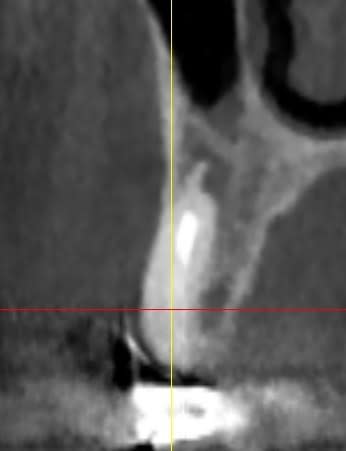

Jeff dans ce cas clinique le plan de traitement a été : empreinte des maxillaires

DVO

Positscan

S.I.A.O

Projet implantaire : extractions, pose de 4 implants, MCI sur 5 implants en récupérant le pilier de l’implant fonctionnel

Validation

Chirurgie

Dans un deuxième temps, les greffes de sinus sont programmées pour la pose de 4 implants

Projet prothétique final : bridge implanto-porté sur 9 implants

Ps : le bridge en pré-op a 15 ans et les implants était bien antérieur.